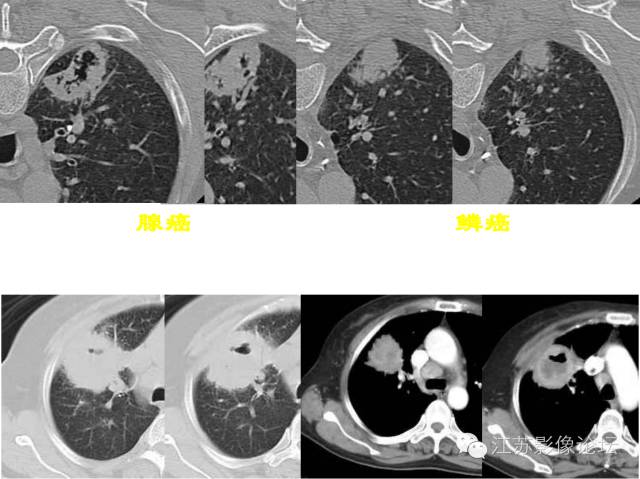

肺部结节的CT鉴别特征

弦距与距长之比>2/5为深分叶;肺癌常见深分叶,错构瘤及结核球可呈浅分叶;炎性假瘤多呈不规则形状。

约90%毛刺结节为恶性结节,部分良性结节边缘也可见毛刺,多为长毛刺及“尖角征”。